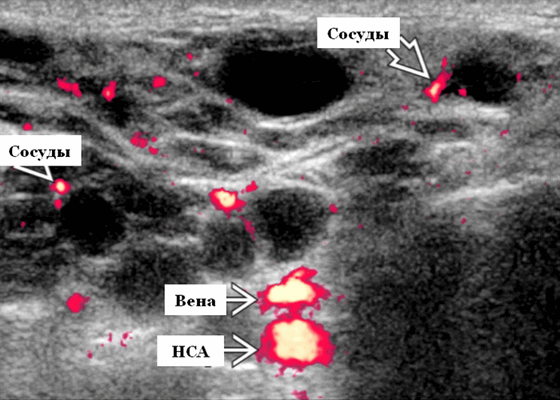

Доброкачественные лимфоэпителиальные поражения (ВИЧ) на УЗИ слюнных желез

- Серошкальное УЗИ. Спектр сонографических находок от простых кист до смешанных и солидных образований. Кистозные, смешанные и солидные поражения могут возникать одновременно в околоушных железах. Кистозные поражения (кисты ДЛК). Хорошо очерченная киста, разного размера, от анэхогенной до гипоэхогенной структуры с задним акустическим усилением. Сеть тонких перегородок ± муральные узлы. Часто встречаются внутренние эхо, которые могут быть мобильными. Сотовидная внешность паренхимы околоушной железы, когда она диффузно изменена з а счет кист. Смешанные поражения (ДЛП). Границы могут быть плохо очерченными, разного размера. Структура преимущественно гипоэхогенная, железы могут быть неоднородными. Без заднего акустического усиления. Солидные поражения (околоушная лимфаденопатия). Множественные овальные / круглые, гипоэхогенные, внутрипаротидные лимфоузлы на УЗИ. Четкий корковый слой ± сохранная корневая архитектура. Сопутствующая реактивная шейная лимфаденопатия

- Цветной допплер. Кистозные поражения: от бессосудистого до умеренного сосудистого кровотока в перегородках, интрамуральных лимфоузлах и на периферии. Смешанные поражения: переменная, васкуляризация от легкой до умеренной. Солидные поражения: внутрипаротидная васкуляризация.